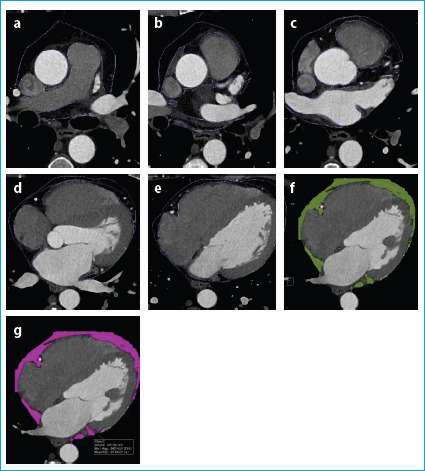

Methods: We retrospectively evaluated a total of consecutive 688 patients who were either asymptomatic but had a positive family history or had typical or atypical symptoms suggesting the presence of CAD. They all underwent CCTA examination with multiplanar reformat (MPR), maximal intensity projection (MIP), and myocardial three-dimensional (3D) volume rendering (VRT) images were obtained. We calculated CCS, coronary artery plaque stenosis degrees, the number of main coronary arteries involved and the EFVs for each patient. Finally, the relationship between the EFVs and all other parameters was analyzed by performing the Pearson and Spearman correlation analysis.